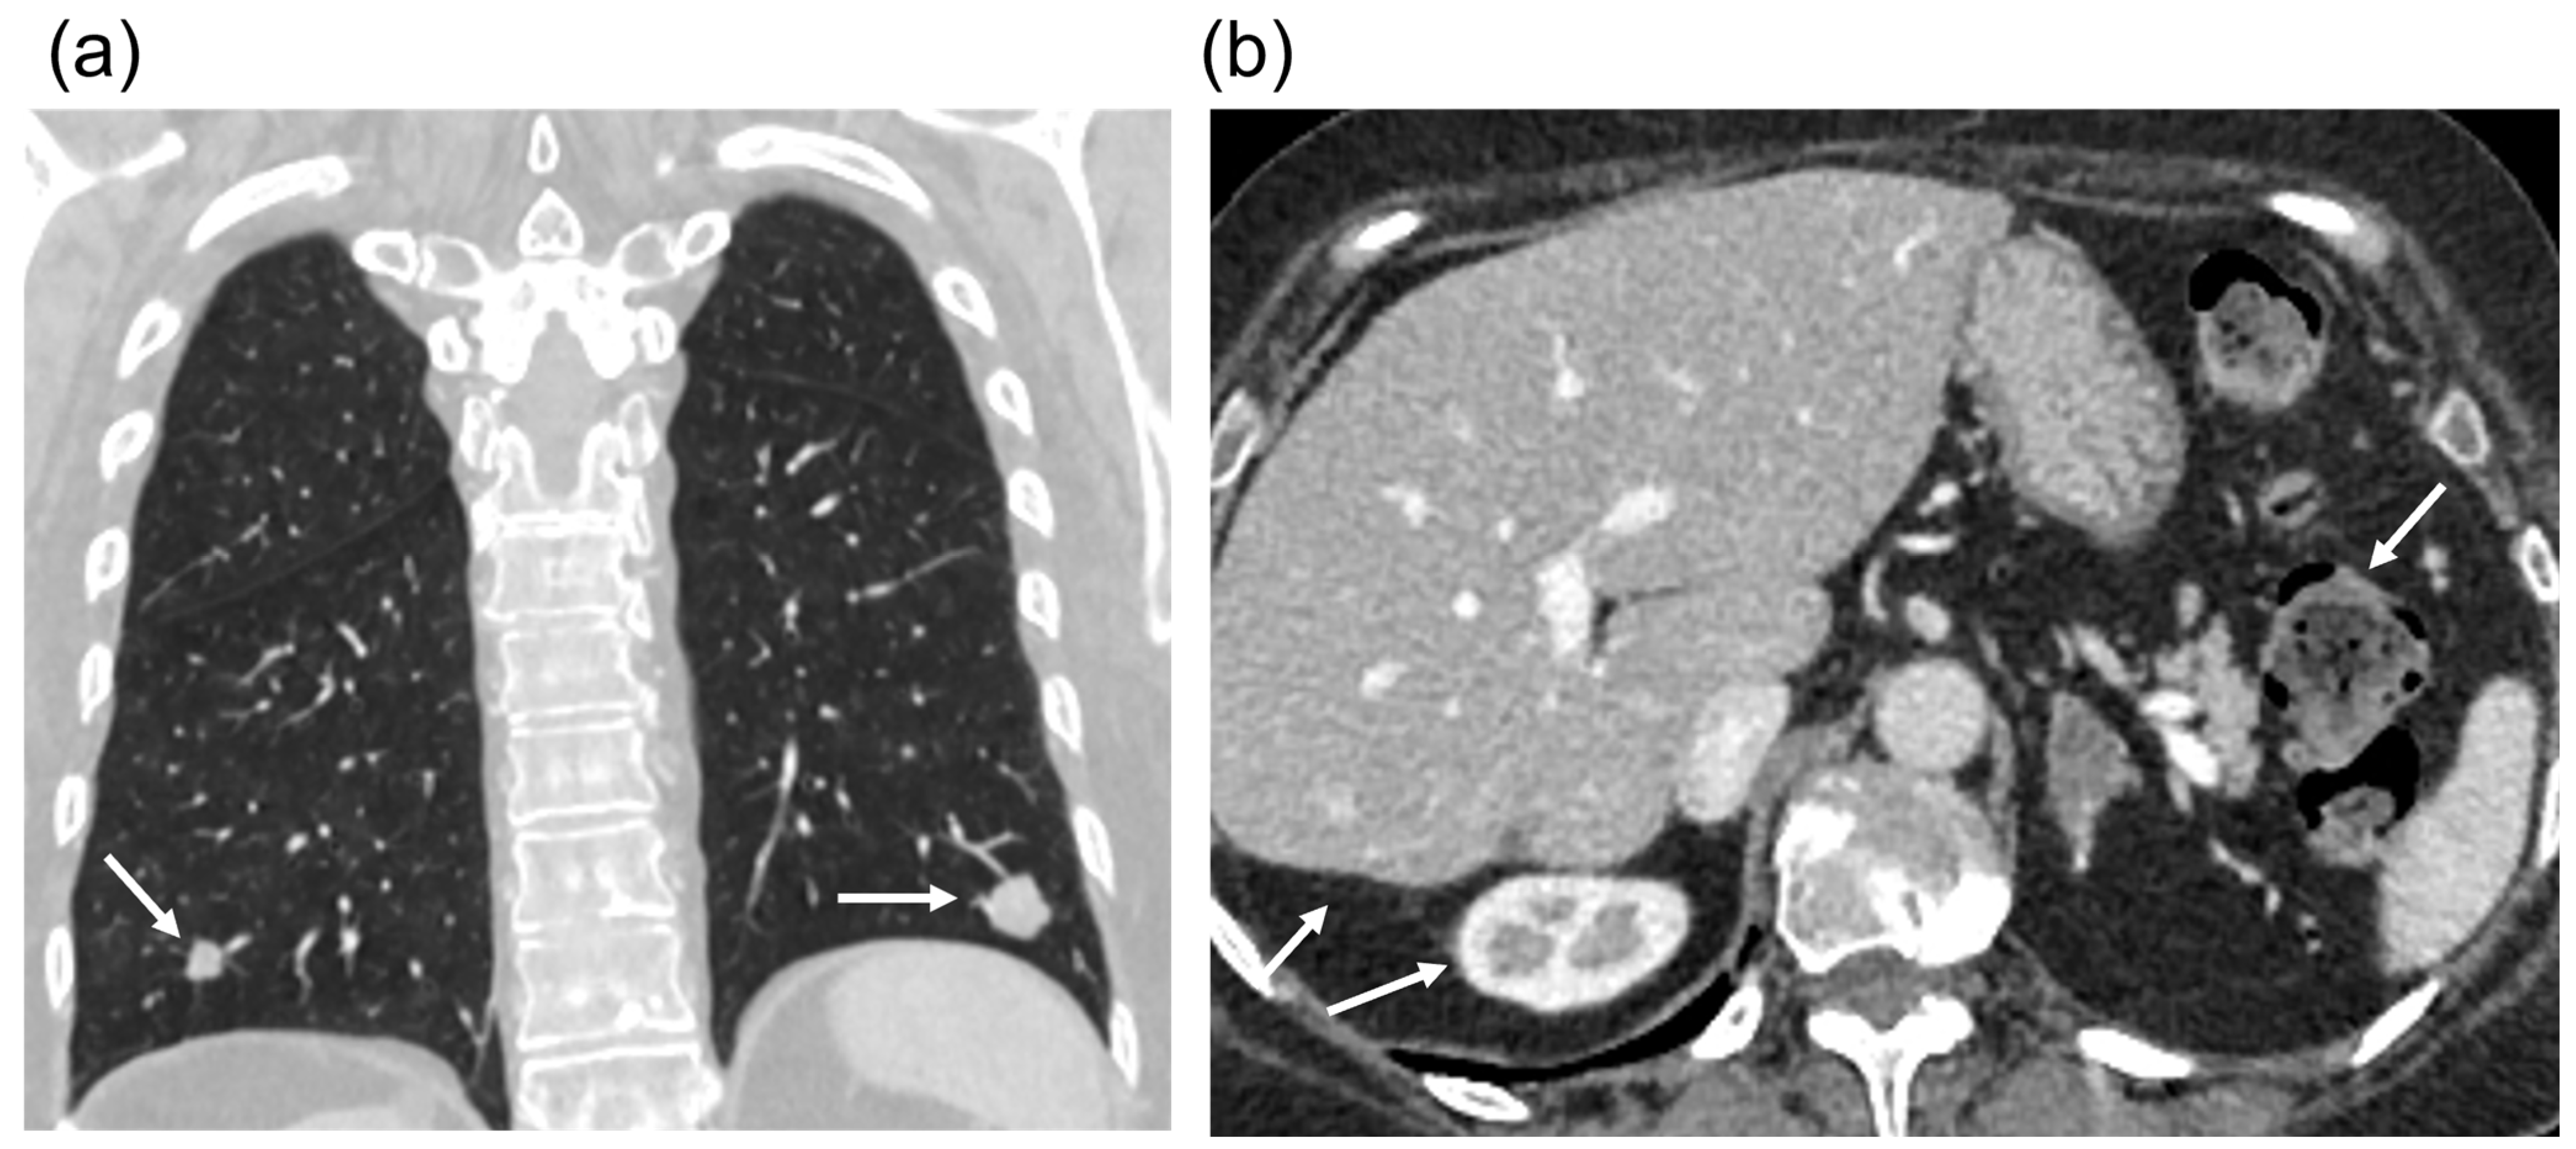

2.1. Case Presentation and Clinical Follow-Up